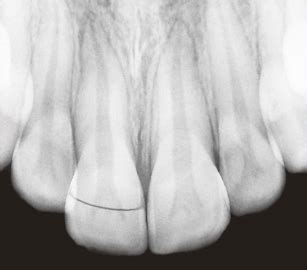

Vertical root fractures have been described as longitudinally oriented fractures of the root 9a. Clinical findings usually reveal a mobile coronal fragment attached to the gingiva. An enamel, dentin, and cementum fracture with or without pulp exposure. A crown root fracture (crf) is a type of dental trauma, which involves enamel, dentin, and cementum. Vertical root fractures have been described as longitudinally oriented fractures of the root 9a. The chief clinical sign of root fracture is mobility. Root fractures are defined as fractures involving the dentine, cementum and pulp. Enamel and dentin fracture with pulp exposure. Check out other videos on. These fractures are commonly found in weak teeth, teeth that have been treated with a root canal, and other restorative treatments like crown placements. Fractures of teeth may involve the crown, the crown and root, or the root. It generally occurs below the gingival margin and depending on the involvement of pulp. Why do vertical root fractures happen? Fracture strength and survival rate of endodontically treated maxillary incisors with approximal cavities after. They can be characterized by an incomplete or complete fracture line that extends through the long axis of the root toward the apex. This article reports the treatment and. A fracture involving the root structure.